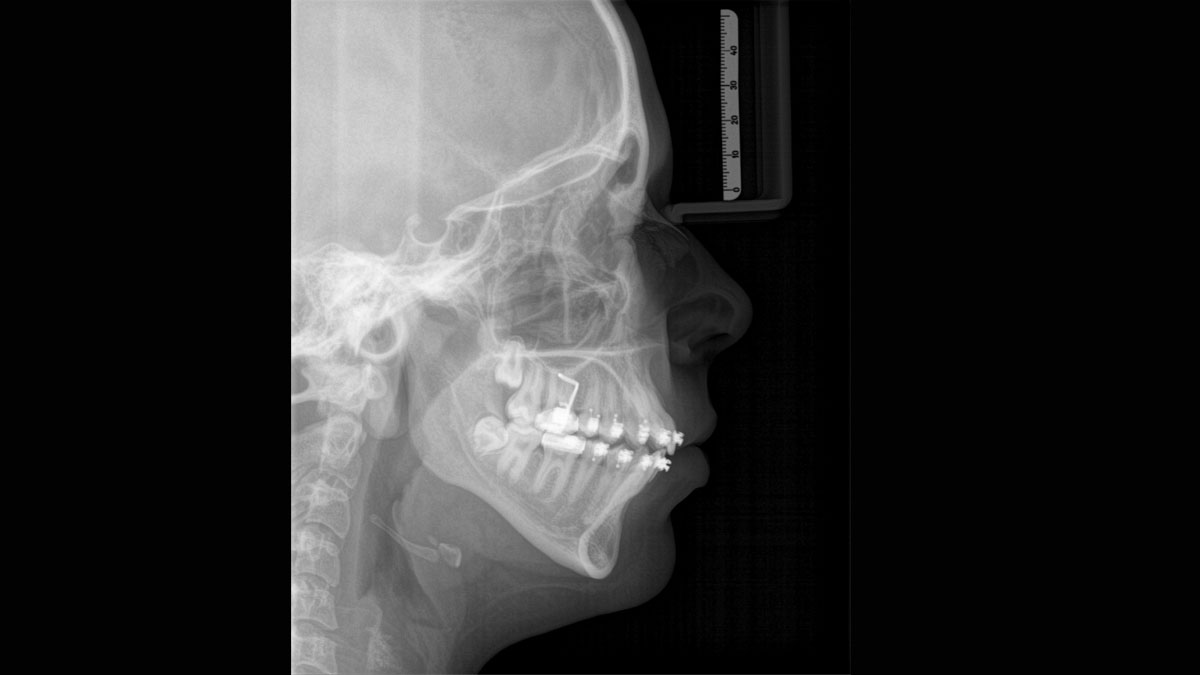

Para imagens panorâmicas excepcionais com alta nitidez. Você pode escolher um braço cefalométrico direito ou esquerdo opcional, que pode ser adaptado a qualquer momento

O foco correto é crucial para excelentes radiografias panorâmicas. Com a função de foco automático, você receberá automaticamente uma imagem com a melhor nitidez possível no foco. Os dispositivos de imagem da Dentsply Sirona capturam milhares de imagens individuais em um ciclo e identificam automaticamente as áreas onde a mandíbula está posicionada de modo ideal. Sem nenhuma etapa manual adicional, essas imagens são exibidas em uma imagem nítida final.

Apenas algumas partes da imagem são focadas, enquanto outras áreas estão desfocadas.

O sistema detecta as áreas relevantes de vários milhares de imagens individuais em um ciclo e identifica automaticamente as áreas onde a mandíbula está posicionada de modo ideal.

Imagens nítidas.